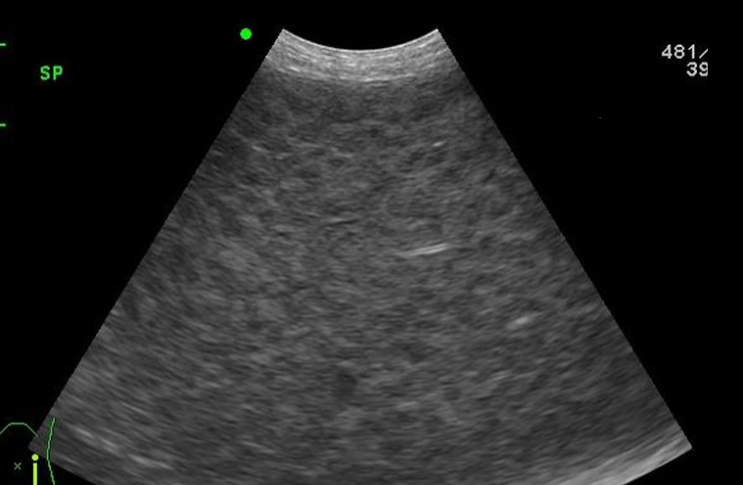

- Variable size / Fine texture / Hyperechoic

✴️ Splenic lymphoma에 대해

초음파 소견

- Hepatosplenomegaly, honey-comb appearance 나타남. (honeycomb=lymphoma는 아님)

- Focal한 mass가 생길 수 있음.

☑️ 체표 림프절 종대 및 기력저하로 내원한 10년령 웰시코기에서 비장 초음파상 소견을 간략히 쓰고, 가장 가능성이 높은 진단명과 감별목록을 작성하시오.

- Splenomegaly, Honey-comb, swiss chesse appearance

- Dx) Splenic lymphoma (뚜렷한 저에코성의 honey-comb)